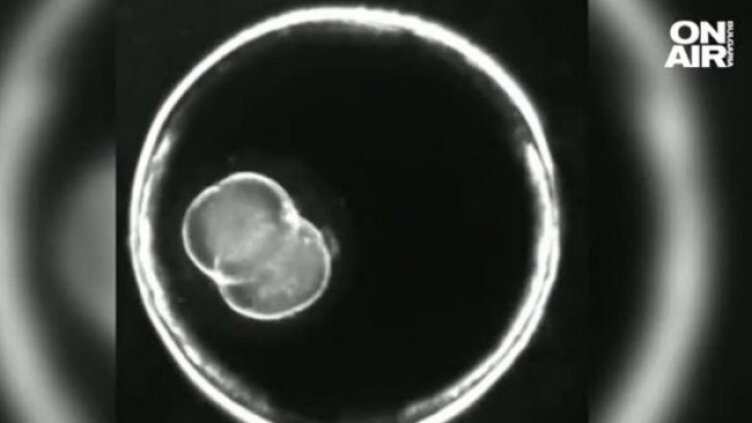

Без участието на сперма или яйцеклетка, учени създадоха синтетичен ембрион на мишка. Проучването, публикувано в реномираното научно издание "Нейчър", дава надежда на много семейства, които не могат да имат биологични деца, предаде Bulgaria ON AIR.

След 10-годишни експерименти учените успяват да създадат ембрион, който започва формирането на органи, без да се използва генетичен материал от родителите. Единствено нужни са стволови клетки. Ембрионът успява да развие всички компоненти за поддържането на жив организъм - мозък и биещо сърце.